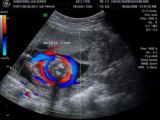

«Να αναφερθώ στην Όλγα Πηλιάκη η οποία, όπως πολύ καλά γνωρίζετε, βρίσκεται στην κλινική τις τελευταίες ημέρες. Βρίσκεται και απόψε στην κλινική. Λόγω ενός ιατρικού θέματος, το οποίο την κράτησε αυτές τις ημέρες εκτός αγώνων, έπειτα από την εξέταση των γι